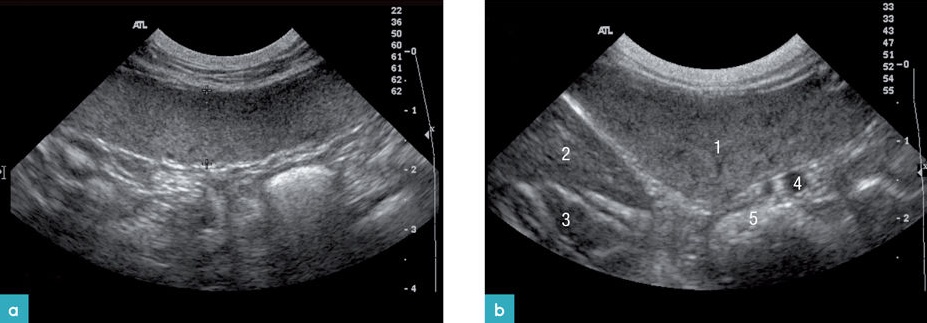

고양이의 비장은 좌측 복벽에서 위의 분문과 가까이 위 아랫부분에 그리고 좌측 신장의 앞쪽 부분에 위치합니다(그림 1).

비장을 스캔하기 위해, 환자의 위치를 우측 외측상 혹은 등쪽을 눕힌 자세(dorsal recumbency)로 위치시킵니다. 비장이 비교적 얕은 부위에 존재하므로 고주파 프로브를 사용하는 것이 좋습니다. 비장은 머리부터 꼬리까지 철저히 횡단면, 종단면으로 스캔합니다.

b) convex transducer로 스캔한 비장. 1. 비장, 2. 위의 내강, 3. 위의 추벽

스캔 시 비장의 모양은 혀(tongue) 모양을 가지며, 꼬리부분이 머리 부분과 몸통보다 넓습니다. 횡단면은 삼각형 모양으로 개의 비장보다 작으며, 위치가 일정합니다. 비장의 머리 부분은 위비장 인대에 의해서 위에 고정되어 있으며, 몸통과 꼬리는 많은 유동성이 있으나, 그 유동성의 정도는 개보다 적습니다. 건강한 고양이에서 비장은 얇고, 고에코성의 캡슐표면으로 부드러운 모양으로 잘 확인이 되며, 깨끗한 경계 부위를 가집니다. 비장의 실질은 치밀하고 동질성의 미세한 과립성의 echotexture를 가집니다(그림 2).

비장의 에코성(echogenicity)은 간과 신장의 에코성과 비교에서 간보다는 높고, 신장보다는 약간 낮습니다(그림 3). 2), 3)